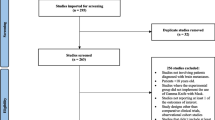

Our exploration of various databases yielded 499 studies, from which 117 were excluded due to duplication. After the initial screening, 382 studies underwent title/abstract screening, which excluded 329 studies. Eventually, 53 studies underwent a full-text screening. Eighteen studies were excluded from the full-text assessment due to the non-English studies (n = 2), wrong population (n = 5), wrong design (n = 7), and not reported outcome (n = 4). Ultimately, 35 studies were included for data extraction and synthesis. The details of the whole study selection process are summarized and depicted in Fig. 1.